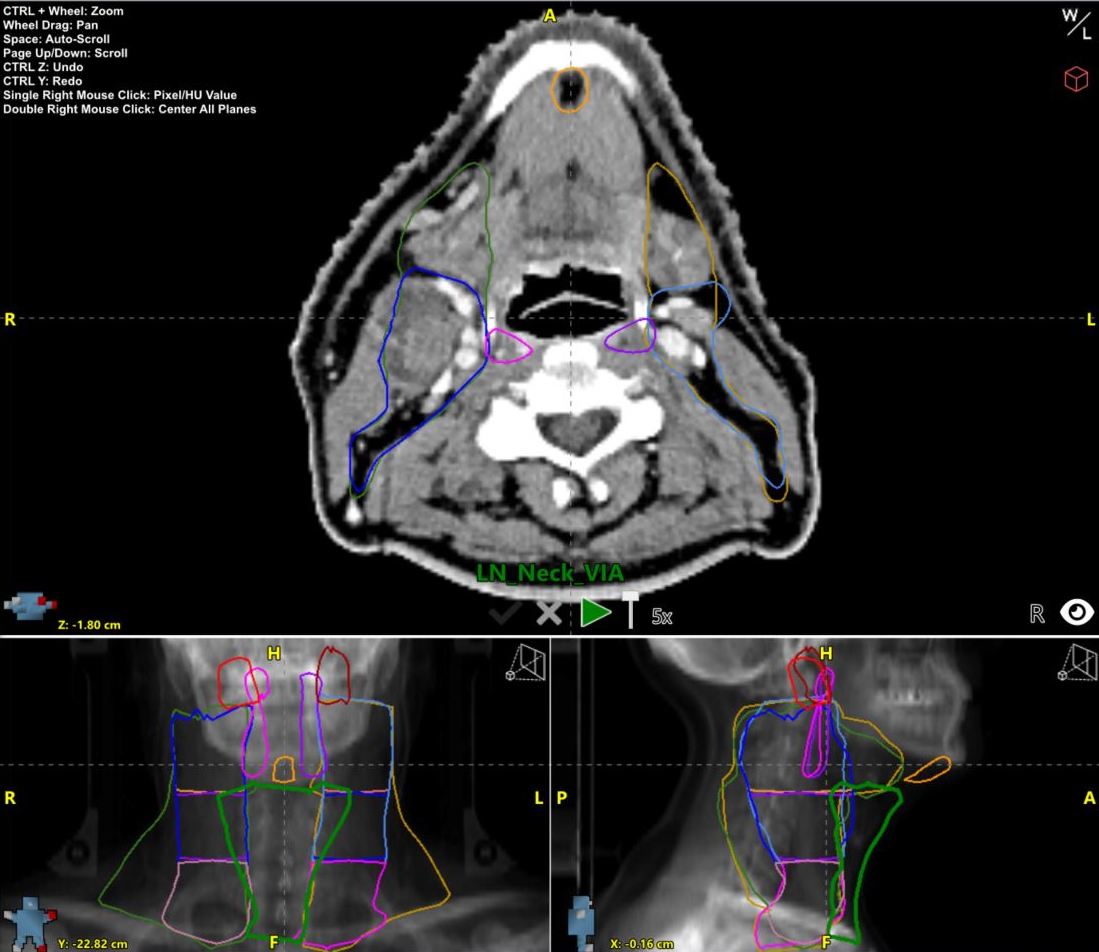

Automated Precision: The Revolution Enhancing Treatment Planning Workflows